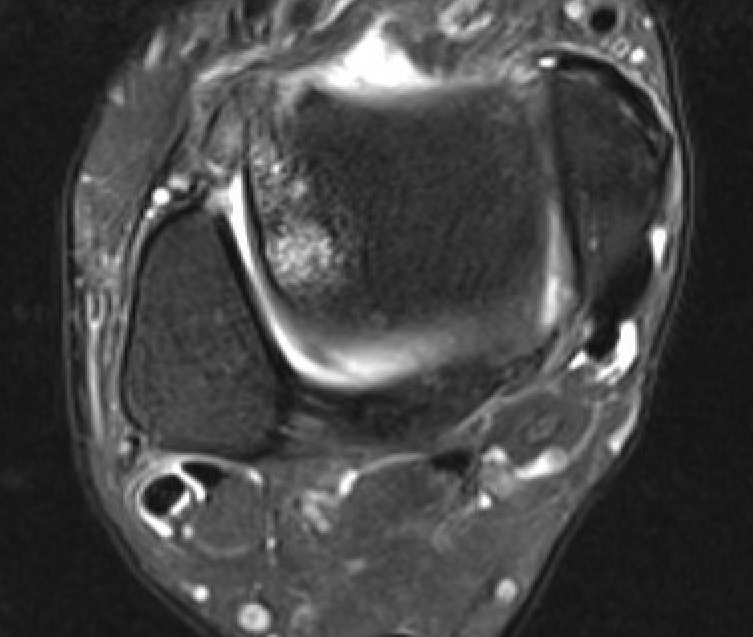

Findings

- tendonitis - fluid around tendons

- tendinopathy - tendon thickening

- tears

Tendinopathy - thickened PL

Peroneal brevis tears